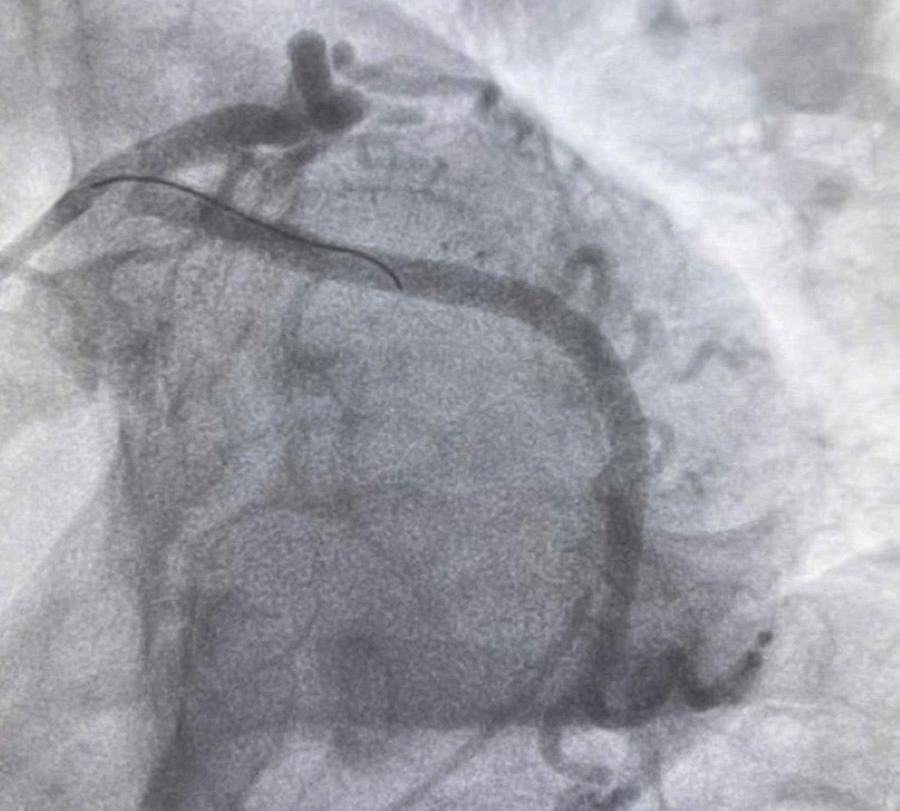

Bác sĩ Khoa Cấp cứu chống độc đã liên hệ hội chẩn Khoa Nội tim mạch, kết luận bệnh nhân bị nhồi máu cơ tim cấp vùng sau dưới và được chụp động mạch vành cấp cứu. Kết quả cho thấy bệnh nhân hẹp khít kèm huyết khối động mạch mũ (1 trong 3 nhánh động mạch vành) nên dẫn tới nhồi máu cơ tim vùng sau dưới.

Sau khi được can thiệp tái thông mạch vành, đặt stent cho bệnh nhân, động mạch mũ được thông tốt. Sau gần 1 tuần điều trị, bệnh nhân đã tỉnh táo, huyết động ổn định, tình trạng đau ngực không còn, có thể xuất viện trong vài ngày tới.